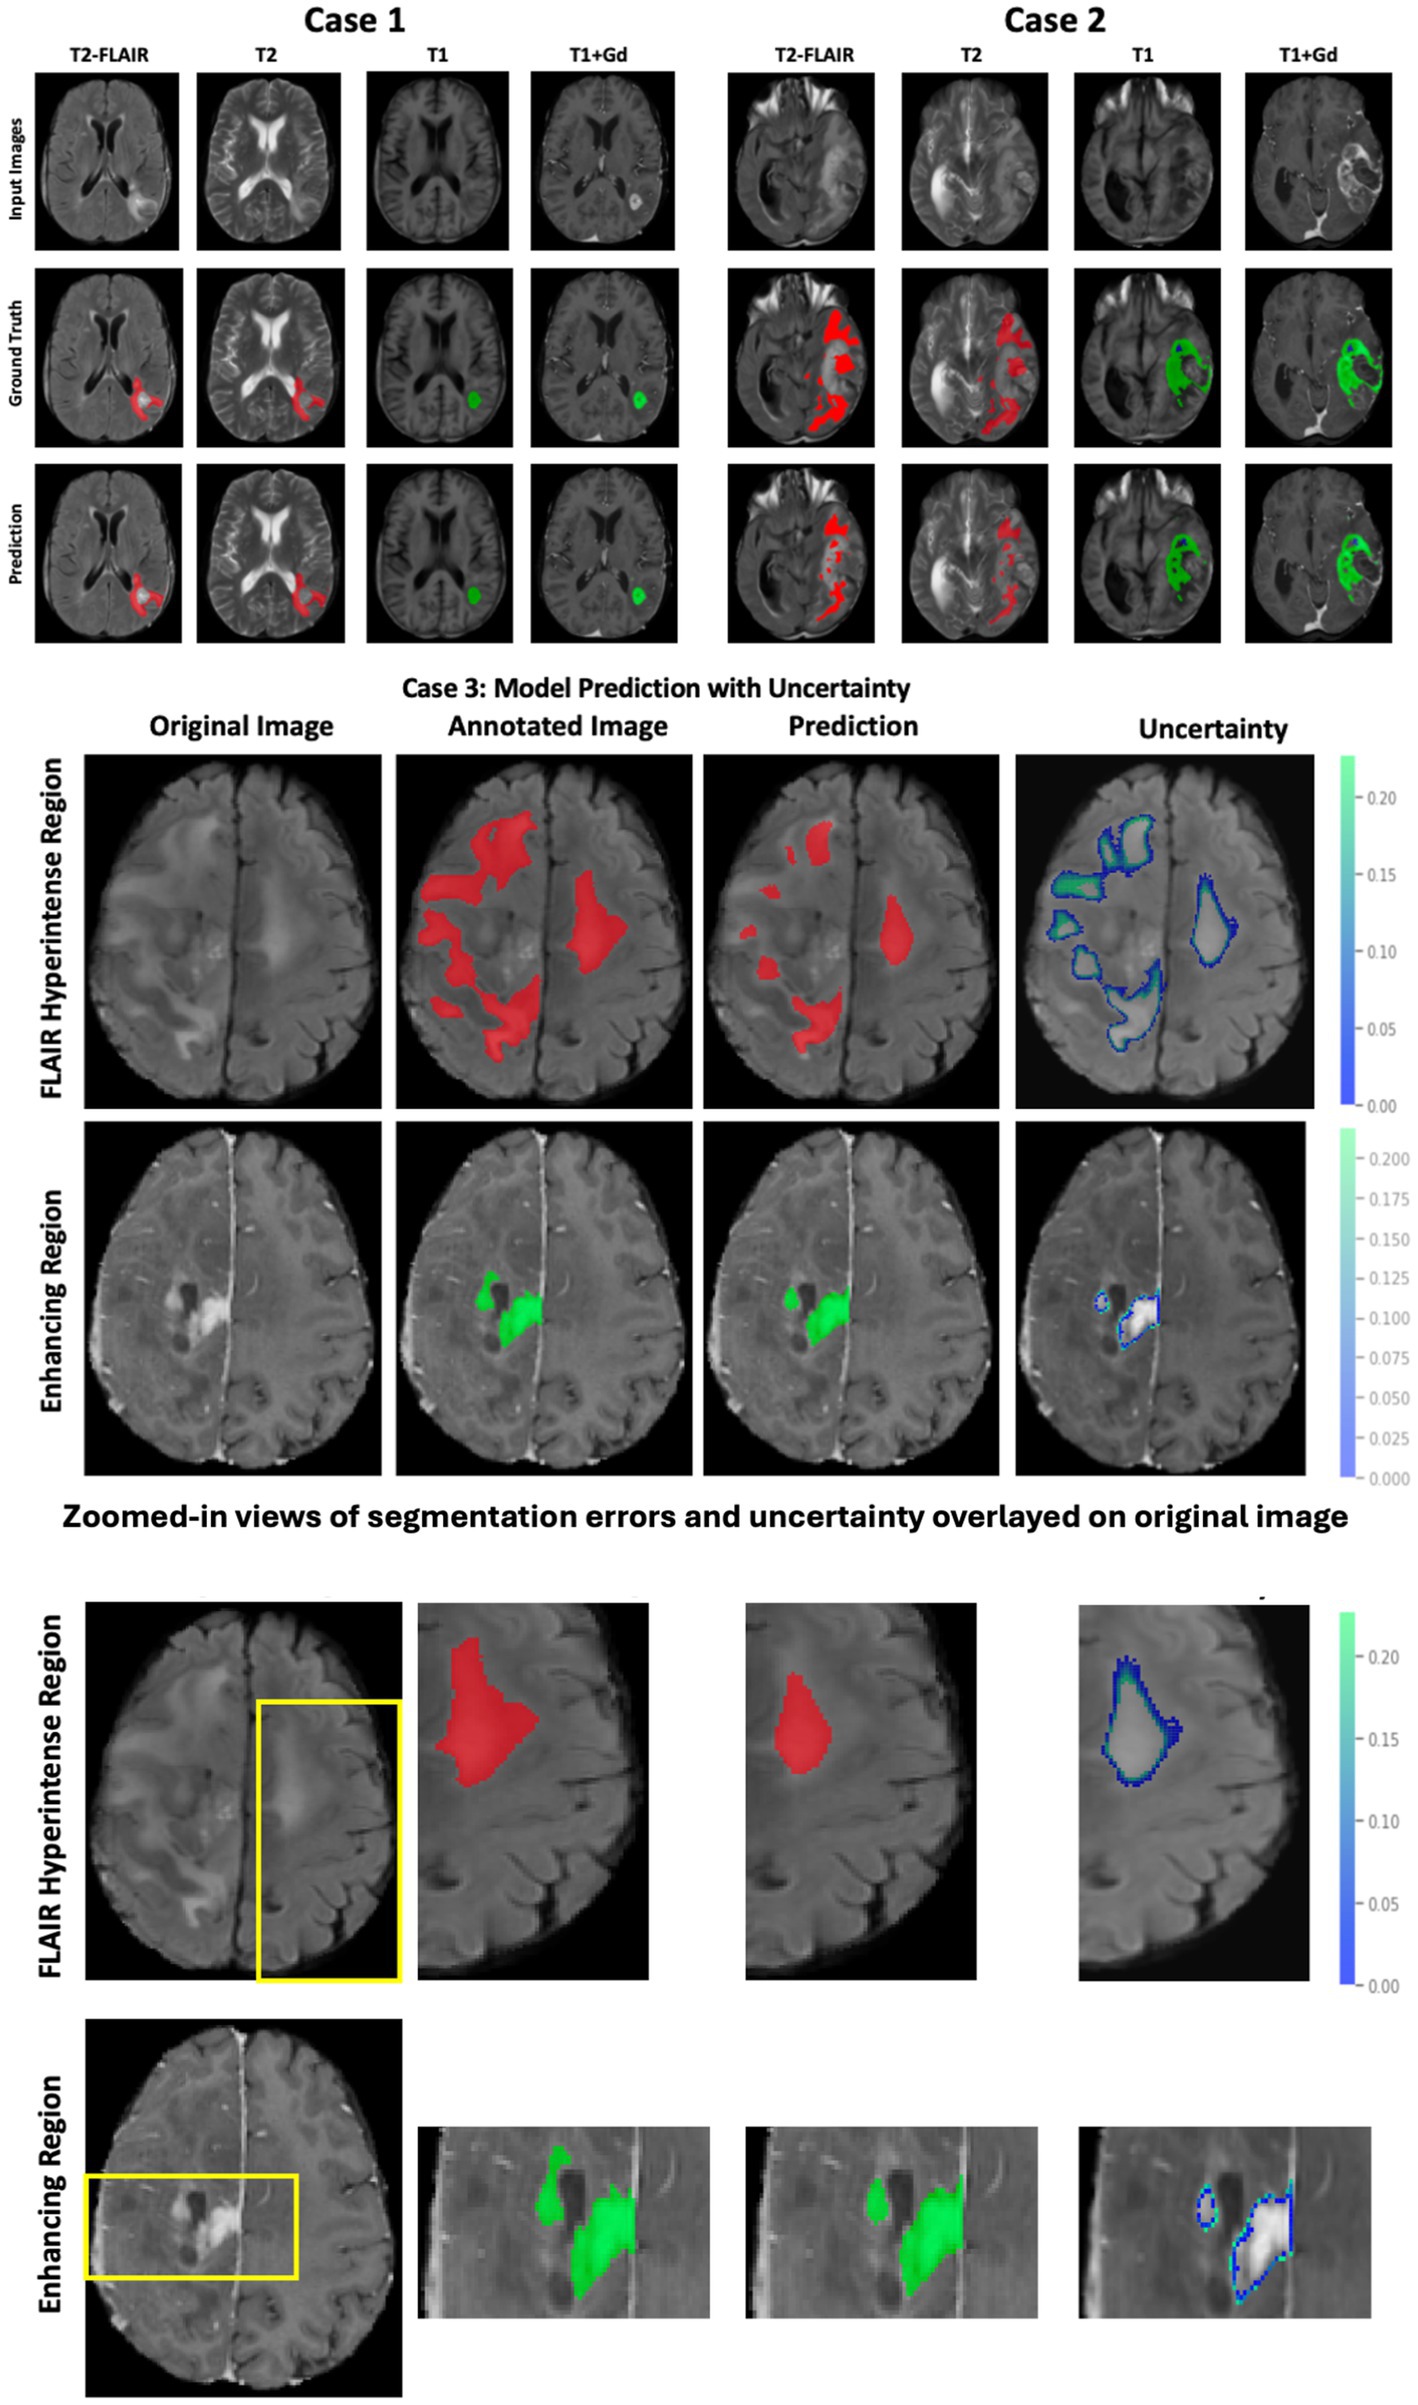

Figure 4 illustrates the follow-up model performance on two cases: Case 1, a well-performing case, and Case 2, a case with underperformance. The DSC for case 1 is 0.92 (FHR), 0.91 (ER), and 0.98 (NENR). In contrast, for Case 2, the DSC values are 0.76 (FHR), 0.82 (ER), and 0.85 (NENR). The shape and structure of the tumor subregions largely influence this performance variation. Case 1 exhibits a continuous shape for tumor subregions, whereas case 2 displays fragmented FHR and ER regions, which impact the model’s performance. Additionally, we report the uncertainty of the model prediction (Figure 3, case 3) to highlight the proposed model’s reliability and trustworthiness. The highest uncertainty was observed at the boundaries of the tumor subregions, indicating regions where segmentation errors are more likely to occur.

Figure 4. Brain tumor segmentation results using the proposed model. Top panel (Case 1 and Case 2): Input MRI modalities, corresponding ground truth annotations (red: FLAIR hyperintense region; green: enhancing tumor; blue: non-enhancing central necrosis), and model predictions. Middle panel (Case 3): Predictions with associated uncertainty maps for the FLAIR hyperintense region (top row) and enhancing region (bottom row), where uncertainty values highlight areas with a higher likelihood of misclassification. Bottom panel: Zoomed-in views of selected regions of interest (ROIs) demonstrate segmentation errors more clearly. In these magnified panels, overlays show mismatches between ground truth and prediction, as well as uncertainty contours highlighting boundaries prone to misclassification.